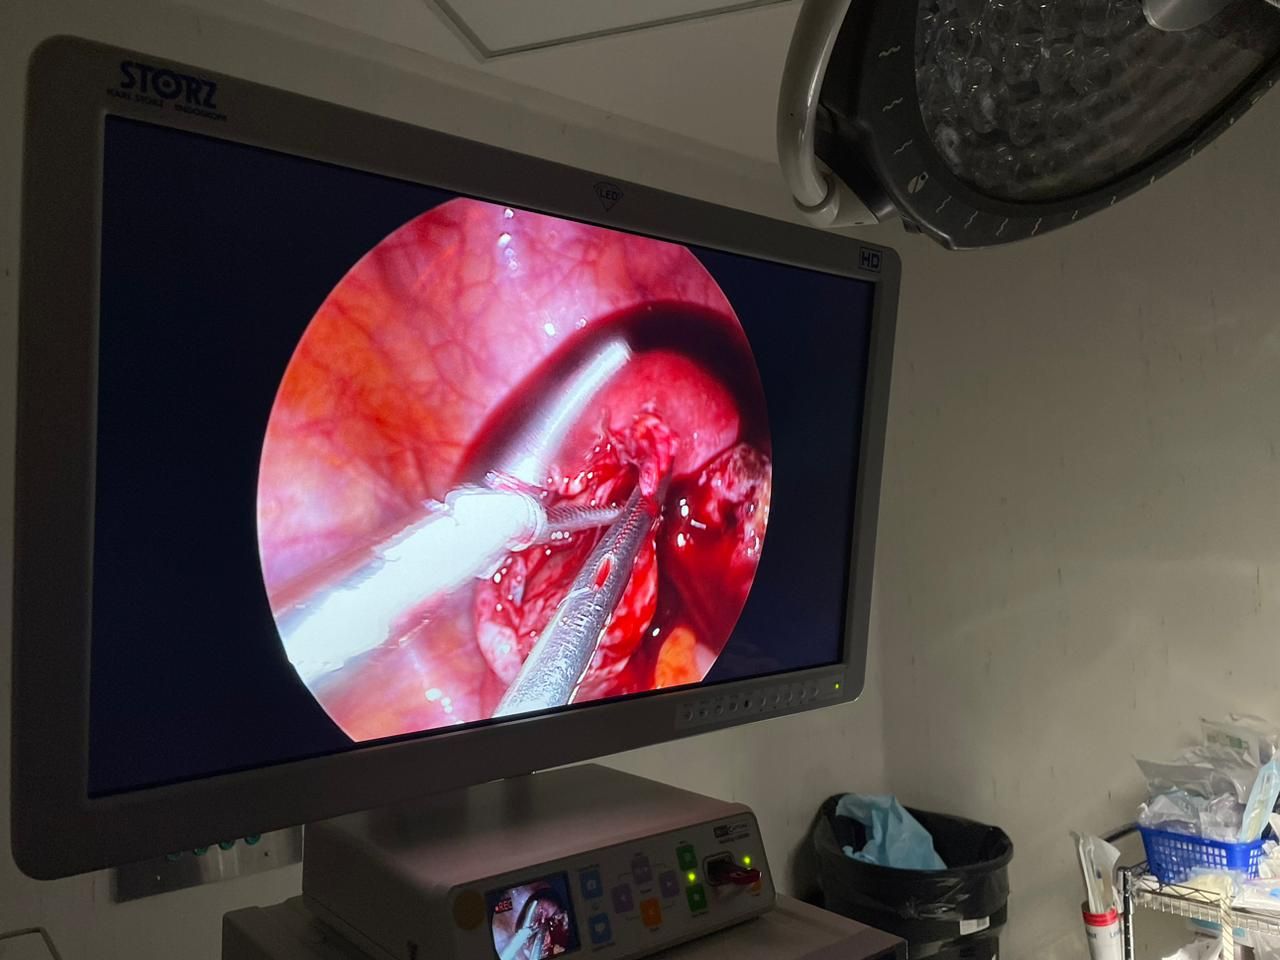

Fotos y videos